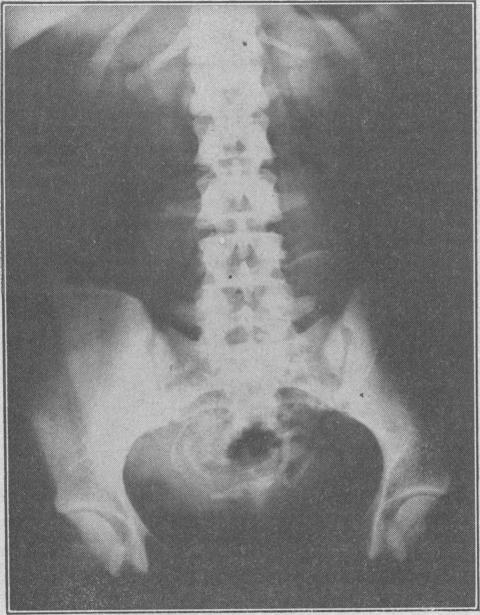

Renal agenesis and severe urinary tract dysplasia: a review of 50 cases, with particular reference to the associated anomalies.

Br Med J. 1960 Mar 19;1(5176):841-6. doi: 10.1136/bmj.1.5176.841.